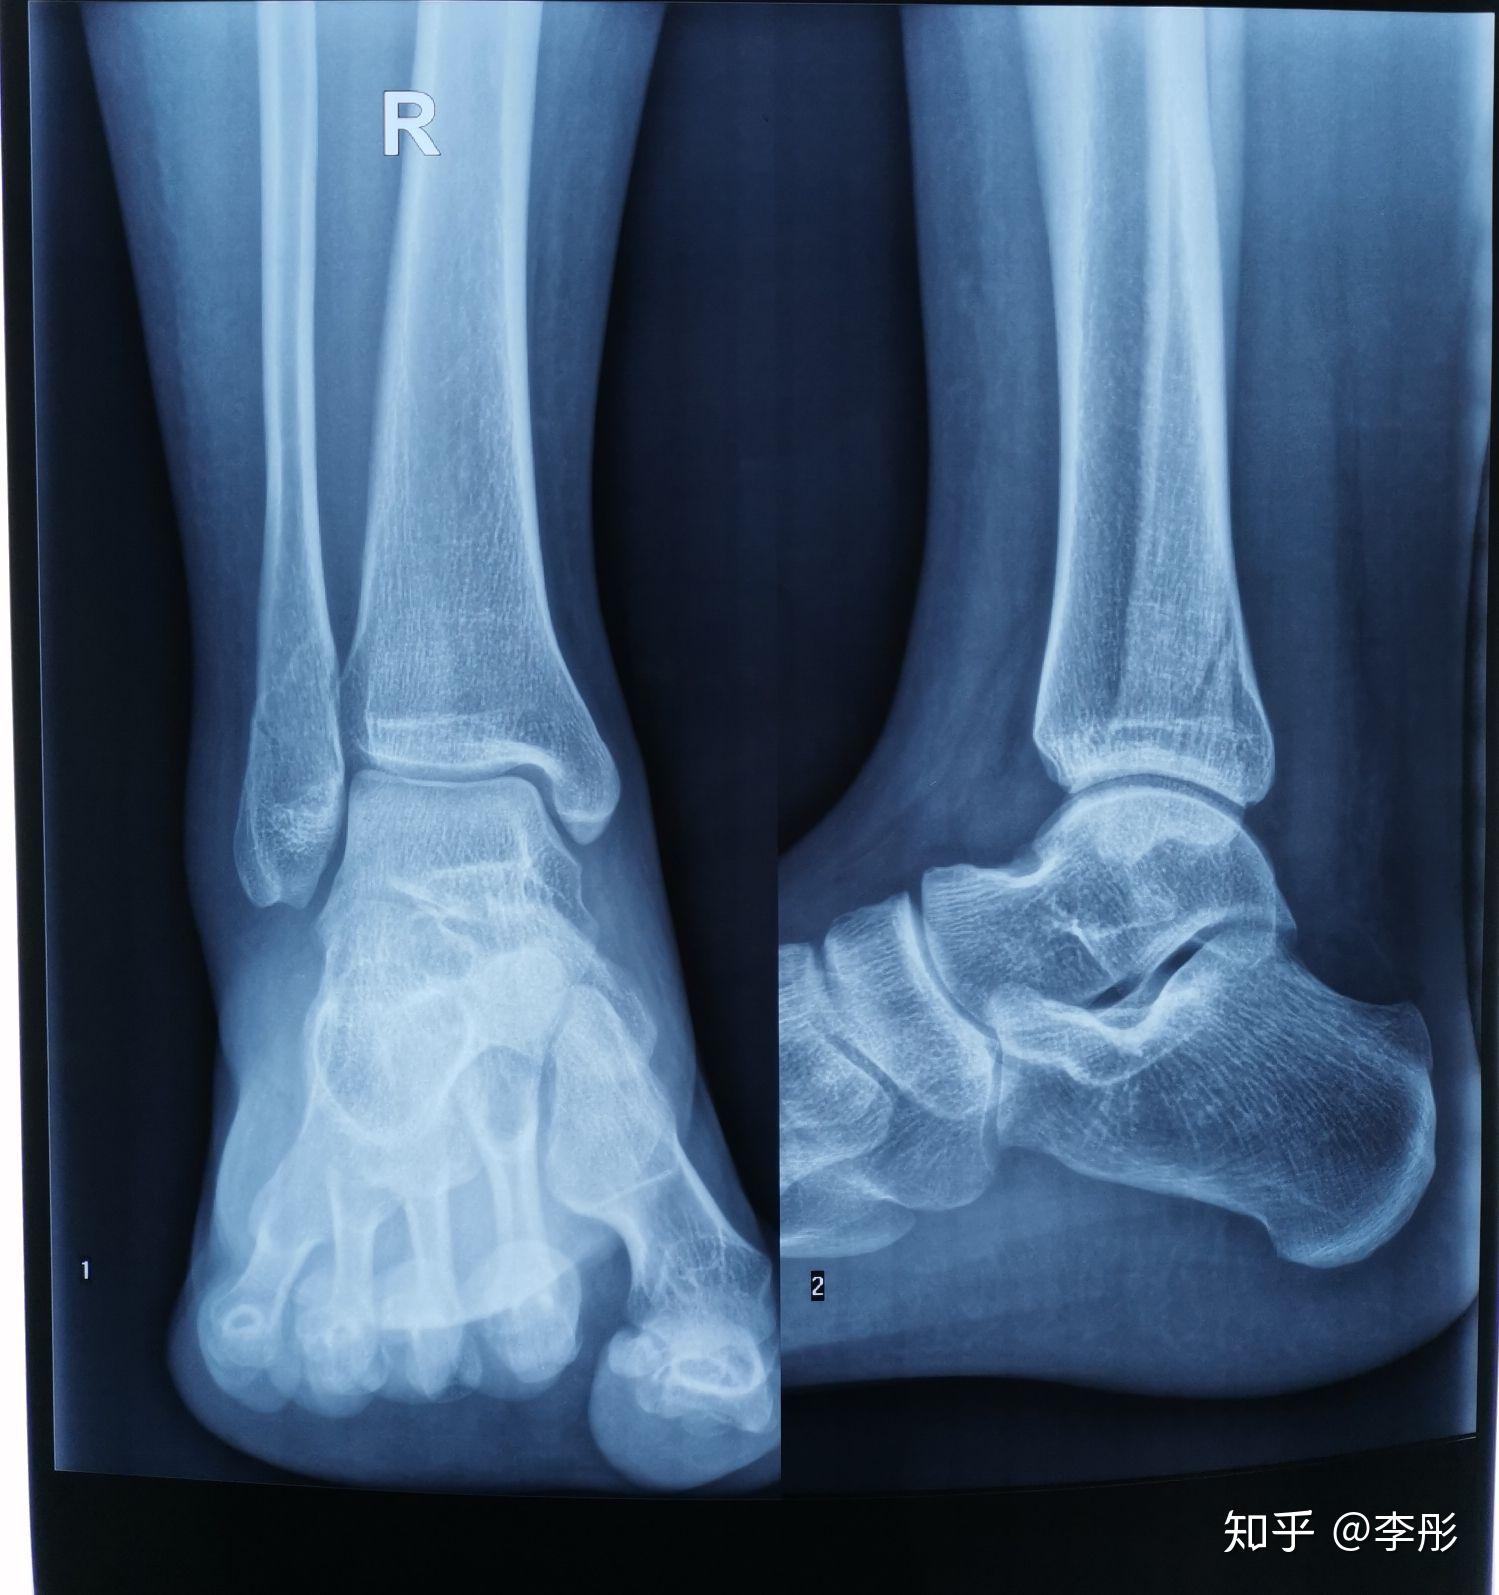

问题:胫腓骨骨折

图片尺寸2448x3264